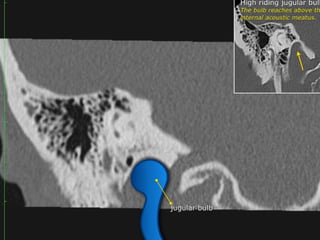

CT Temporal Bone Search Pattern with selected images :

Other structures/landmarks:

•Styloid process

•Stylomastoid foramen

•Petrous apex

•Mastoid air cells

•Sigmoid sinus

•Cochlear promontory

•Carotid canal

•Tegmen

•Jugular bulb